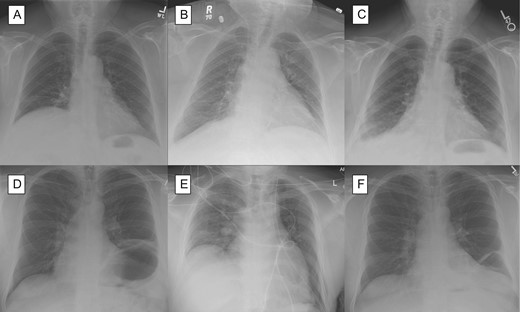

The first case is a 70-year-old female with progressive shortness of breath. The patient had a CXR that showed an elevated right diaphragm (Fig. 1A) and sniff test showed a paralyzed right diaphragm. She underwent diaphragm plication (Video 1). On post-operative Day 1 (Fig. 1B) and 1 month follow-up (Fig. 1C), there was no longer an elevated right diaphragm.

Chest X-ray for patient with right diaphragm paralysis (A) after repair on post-operative Day 1 (B) and after 1 month (C) as well as chest x-ray of patient with left diaphragm paralysis (D) after repair on post-operative Day 1 (E) and after 1 month.

The second case is a 44-year-old male with progressive shortness of breath over a year. The patient stated that his dyspnea had worsened over the past year. The patient had a CXR that showed an elevated left diaphragm (Fig. 1D) and sniff test showed left diaphragm paralysis. The patient had diaphragm plication. On post-operative Day 1 (Fig. 1E) and 1 month follow-up (Fig. 1F), there was no longer an elevated left diaphragm.